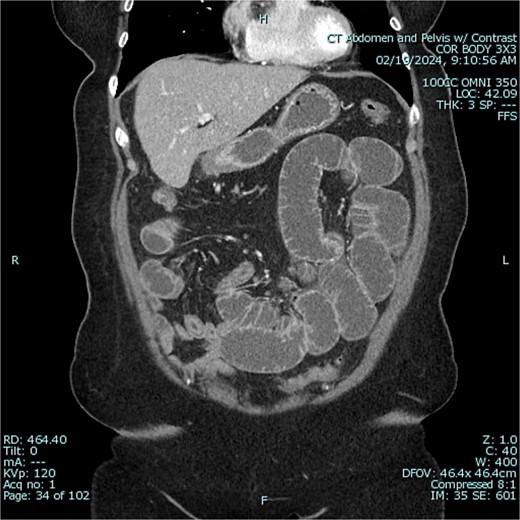

The patient was admitted to the hospital for conservative management of suspected adhesive SBO. She was treated with intravenous fluid hydration and nasogastric tube decompression. On hospital days 2–4, she began to feel better and pass flatus. Gastrografin challenge revealed passage of contrast through the small intestine and into the colon (Figs 3 and 4). On hospital day 5, however, she had cessation of bowel function with worsening abdominal pain, tachycardia, and leukocytosis (WBC 16 K/μl).

Gastrografin challenge reveals passage of contrast through the small intestine and into the colon on sequential imaging [297 × 360 mm (72 × 72 DPI)].